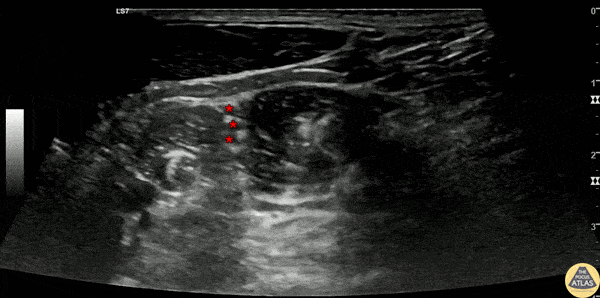

20s M with history of shoulder dislocations in the past presented with shoulder pain after boxing. He had a visible deformity to the shoulder, and radiographs confirmed an anterior glenohumeral dislocation. After documentation of a neurovascular exam, an interscalene nerve block was performed to facilitate reduction. The block is shown here, first with identification of the brachial plexus nerve roots (*) between the anterior and middle scalene muscles. The second part of the clip shows injection of anesthetic in the interscalene groove adjacent to the nerve roots. This patient had quick pain relief and closed reduction was achieved easily without sedation. Tanner Muggli, PGY1 Denver Health Residency in Emergency Medicine